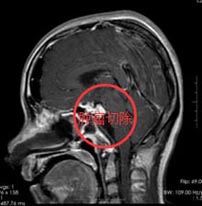

在广东三九脑科医院综合神经外科,经鼻蝶鞍神经内镜下行颅咽管瘤切除术,术程顺利,肿瘤全部切除。

术后患周女士视力没有任何影响,术后第二天便可坐起,并正常饮食,内分泌功能没有影响。